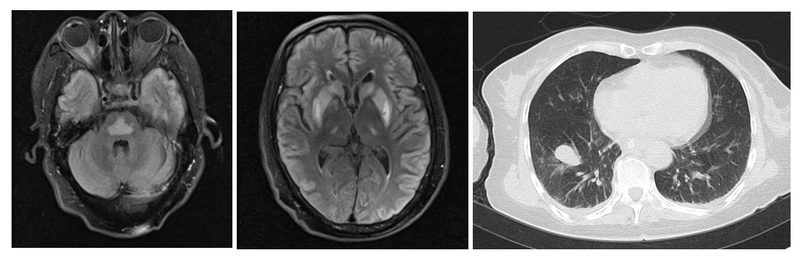

患者,女,58歲,家庭主婦,因“發(fā)熱、咳嗽半個(gè)月,精神行為異常6天,意識(shí)障礙3天”入院。半個(gè)月前,患者無(wú)明顯誘因出現(xiàn)發(fā)熱(最高溫度不詳)、咳嗽,于當(dāng)?shù)蒯t(yī)院住院治療(具體藥物不詳),后患者病情進(jìn)一步加重,出現(xiàn)惡心、伴有數(shù)次非噴射性嘔吐,嘔吐物為胃內(nèi)容,有頭暈不伴有視物旋轉(zhuǎn),病程中反復(fù)低熱。患者子女遂將患者送至xx中醫(yī)院,予以輸液治療后患者頭暈及嘔吐較前進(jìn)一步加重,同時(shí)患者出現(xiàn)無(wú)法排尿困難,當(dāng)?shù)赜枰詫?dǎo)尿留置尿管。6天前,患者出現(xiàn)胡言亂語(yǔ),患者子女遂將患者轉(zhuǎn)至xx中心醫(yī)院,完善頭顱CT:未見(jiàn)明顯異常。胸部CT:右肺下葉及右肺肺門(mén)區(qū)團(tuán)塊影,腫瘤性病變;考慮左肺上葉尖后段、右肺下葉散在感染灶;左肺下葉背段胸膜下肺大皰;完善腰椎穿刺術(shù),腦脊液蛋白:0.15g/L、腦脊液氯化物113.6mmol/L、腦脊液葡萄糖2.76mmol/L;腦脊液白細(xì)胞1.010^6/L。3天前,患者病情進(jìn)一步加重,出現(xiàn)呼之不應(yīng),故患者家屬為求進(jìn)一步診治,遂就診于我院。入院后完善頭顱MRI提示:腦橋、雙側(cè)基底節(jié)區(qū)及丘腦多發(fā)對(duì)稱性異常信號(hào),考慮滲透性脫髓鞘可能。行支氣管檢查最后病理提示肺腺癌?;厮莼颊咴和赓Y料發(fā)現(xiàn),在xx中醫(yī)院時(shí),患者第一次血鈉115mmol/L,給予了積極補(bǔ)鈉治療,間隔24小時(shí)血鈉135mmol/L。結(jié)合患者的整個(gè)病史臨床考慮診斷1、肺腺癌;2、滲透性脫髓鞘綜合征(橋內(nèi)橋外髓質(zhì)溶解癥);3、低鈉血癥。肺癌患者常合并稀釋性低鈉血癥,處理此類低鈉血癥主要是限水治療,或口服托伐普坦。當(dāng)?shù)外c血癥糾正血鈉過(guò)快時(shí),由于Na離子不能盡快進(jìn)入神經(jīng)細(xì)胞,可能引起腦細(xì)胞急劇脫水,導(dǎo)致髓鞘和少突膠質(zhì)細(xì)胞脫失而出現(xiàn)滲透性脫髓鞘綜合征,最常發(fā)生在腦橋,形成腦橋中央髓質(zhì)溶解癥。有時(shí)也可以累及到腦橋外,如基底節(jié)區(qū)。發(fā)生滲透性脫髓鞘綜合征后治療上主要是支持治療,有一些報(bào)道顯示激素和靜脈注射丙球可能有效,但主要還是通過(guò)緩慢糾正低鈉血癥來(lái)預(yù)防。低鈉血癥補(bǔ)鈉要求第一個(gè)24小時(shí)不宜升高超過(guò)10mmol/L,之后每日血鈉升高不超過(guò)8mmol/L。